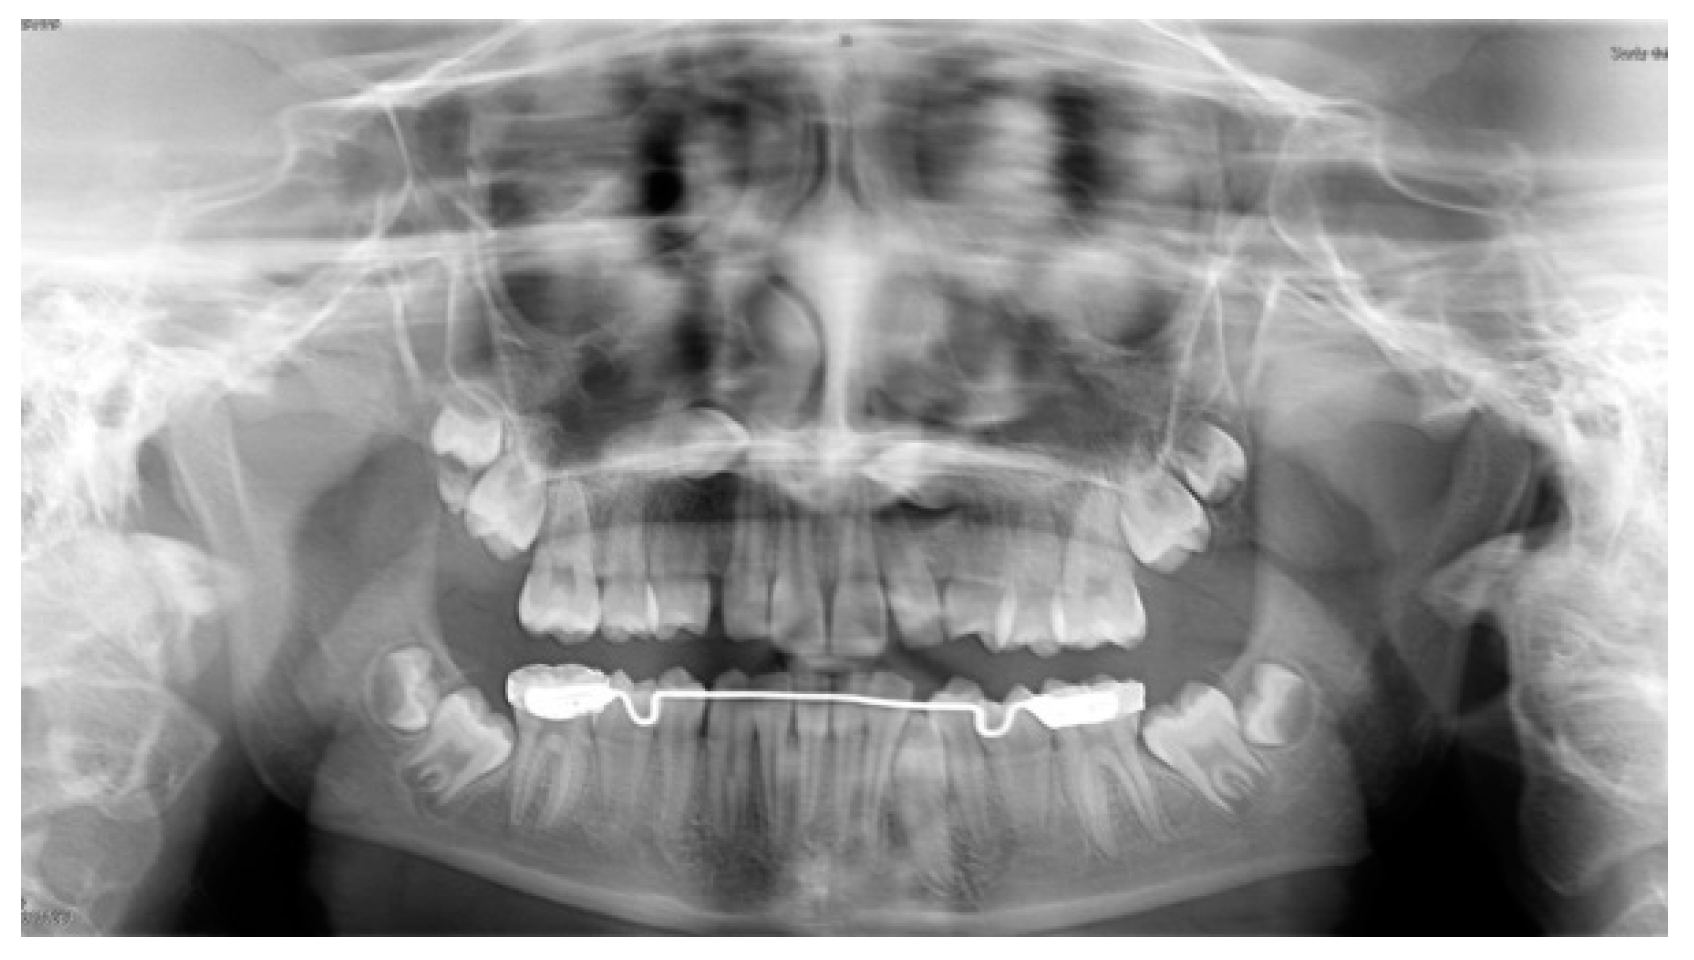

The panoramic radiograph showed the presence of several impacted teeth (Figure 1). Angle of inclination of MM2 was measured, as described by Evans [17]. The angle of the left MM2 was 30°, the angle of the right MM2 was 40°. Cephalometric measurements were performed using lateral cephalometric radiography that showed a Class I skeletal relationship (ANB = 2°), brachyfacial growth pattern (MP-SN = 30.5°; FMA = 17.5°) and palatal inclination of the upper incisors (U1—ANS-PNS = 107.0°).

Figure 1.

Pretreatment panoramic radiograph showing bilaterally impacted MM2 and upper canines.